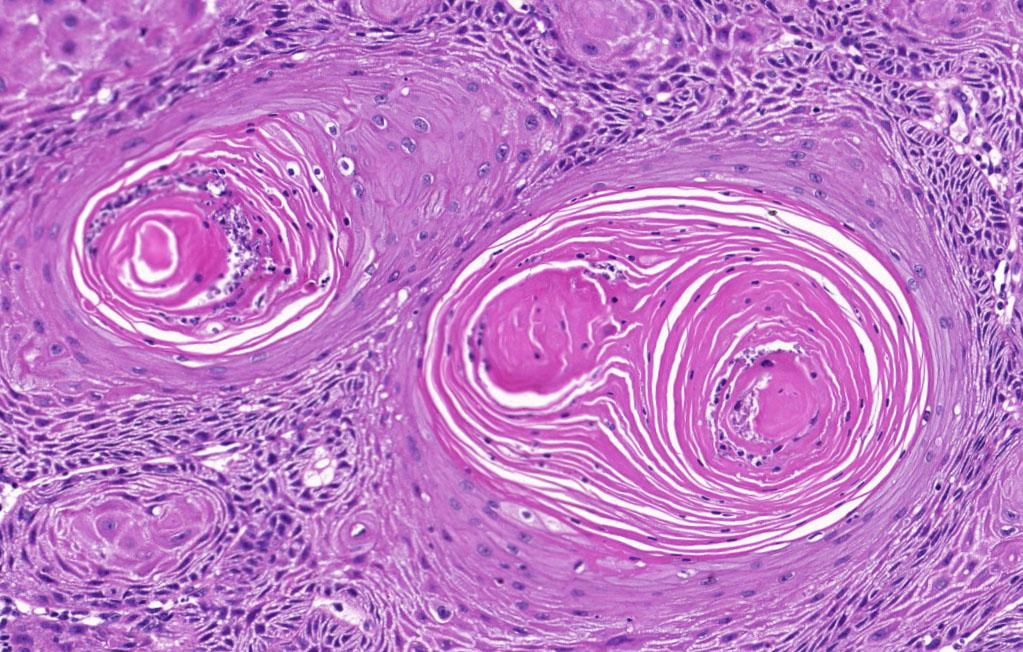

A histopatologia é o exame microscópico de tecidos biológicos para o diagnóstico de doenças, sendo o diagnóstico definitivo (“padrão ouro”) para a maioria dos processos.

O exame histopatológico envolve o exame de uma biópsia (ou seja, uma amostra retirada cirurgicamente por um médico veterinário) e analisado por um médico veterinário especializado, chamado patologista.